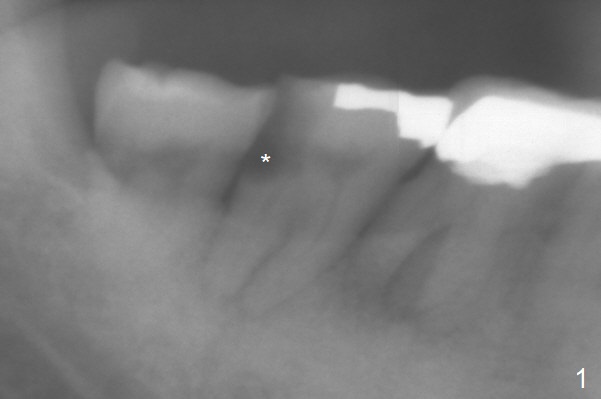

Long Implant

A 72-year-old man has DO subgingival caries (Fig.1 *). He prefers implant over RCT (Fig.2). The tooth #30 has deep pocket or an abscess distlbuccally. Cavitron scaling will be done.